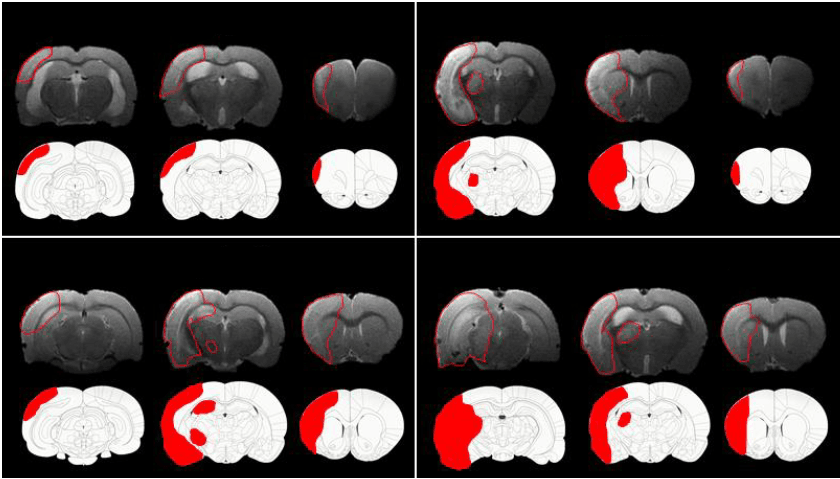

The infarct area, as observed on H&E-stained sections under the light microscope, was manually transcribed onto diagrams of corresponding coronal slices from a brain atlas. These were subsequently scanned into a computer and scrutinised using image analysis software. The area of the drawn infarct was manually delineated, mirroring the method applied for T2-weighted MRI images, but without oedema correction. The infarct area from each diagram was compared with the oedema-corrected and uncorrected infarct areas from the corresponding slices from T2-weighted MRI images of the same brain, to evaluate the precision of infarct measurement from MRI images. Oedema-corrected infarct areas from T2-weighted images were calculated using formulas from previously published research. Lesion areas deduced from diagrams were significantly smaller than those calculated from T2-weighted images prior to oedema correction.